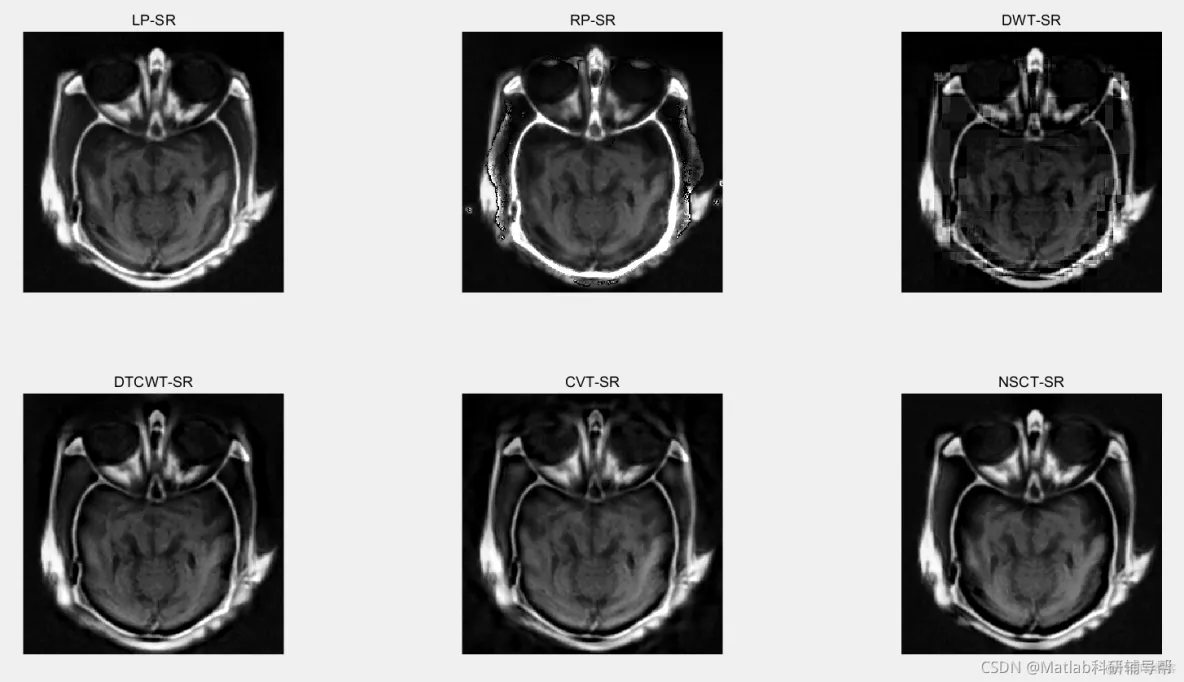

三、仿真结果